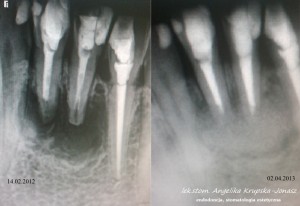

EXAMPLES OF ROOT CANAL TREATMENT PERFORMED BY OUR TEAM

Root canal treatment becomes necessary when the pulp of the tooth is attacked, that is, the tissue filling its interior, which is composed of blood vessels and lymphatic vessels as well as nerve fibers. In some cases, it happens that the tooth does not give pain, and yet there is an irreversible bacterial infection of the pulp. In most cases, patients requiring root canal treatment complain of acute pain in the affected teeth. Endodontic treatment is also necessary in some cases of tooth injury. This method of treatment is also sometimes used due to prosthetic indications. Infected dental pulp and pathological changes occurring in it are sometimes visible on the radiological image, which is performed before the procedure. Thorough cleansing, chemo-mechanical treatment of the root canal and its tight filling, for which special microscope is used, in the vast majority of cases leads to remission of bone changes and bone regeneration.